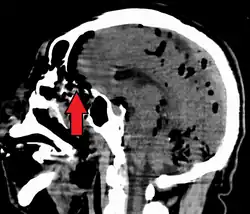

Pneumocephalus is the presence of air or gas within the cranial cavity. It is usually associated with disruption of the skull: after head and facial trauma, tumors of the skull base, after neurosurgery or otorhinolaryngology, and rarely, spontaneously. Pneumocephalus can occur in scuba diving, but is very rare in this context.

If there is a valve mechanism which allows air to enter the skull but prevents it from escaping, a tension pneumocephalus can occur (similar to what can happen in a tension pneumothorax).